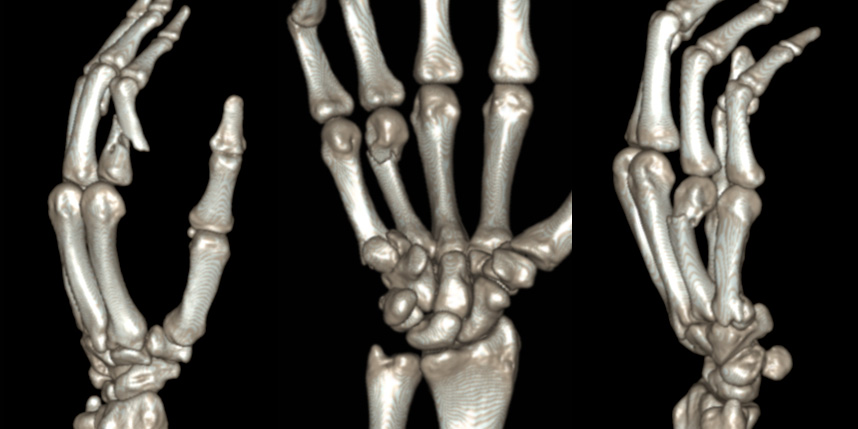

골절은 정확하게 골절편을 잘 맞추고 고정하는 것이 중요합니다. 특히 관절면을 잘 맞추는 것이 중요합니다.

손가락 골절

* 환자에게 받은 소중한 자료입니다.